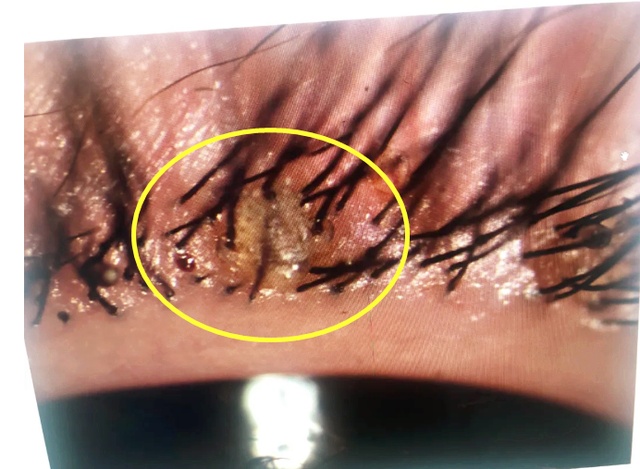

眼睛瘙痒、红肿溃烂…

医生检查发现长满大量虫子

经过显微镜的放大,

范医生在张女士的睫毛根部

发现了好几只蠕形螨,

这就是造成张女士眼睛不适的元凶

——蠕形螨!

影像显示,张女士睫毛上的蠕形螨

养得比较“肥”,还在不断蠕动,

看得人鸡皮疙瘩都起来了,

边上围观的医生发出感慨:好大呀

显微镜下张女士眼部的蠕形螨